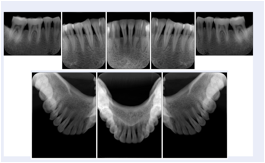

Intra-oral radiography typically involves acquisition of multiple images of various parts of the dentition. Many digital radiographic systems offer customized templates that are used for displaying the images in a study on the screen. These templates may also be referred to as mounts or view sets. The Structured Display Object represents a standard method of encoding and exchanging the layout and intended display of Structured Displays. A structured display object created in this manner could be stored with a study and exchanged with images to allow for complete reproduction of the original exam.

In most standard cases, images are oriented in structured layouts. These structured displays are useful to be shared between providers for reference purposes.

Table OO.1.1-1 shows structured display standard templates, where Viewset ID is based on the Japanese Society for Oral and Maxillofacial Radiology (JSOMR) classification provided by JIRA (Japan Medical Imaging and Radiological Systems Industries Association, www.jira-net.or.jp). Expected or typical teeth to be imaged location, region and designation codes are based on ISO 3950-2010, Dentistry - Designation system for teeth and areas of the oral cavity. For all the hanging protocols listed in OO.1.1-1, the value to use for Hanging Protocol Creator (0072,0008) is "JSOMR" and the value to use for Hanging Protocol Name (0072,0002) does not include "JSOMR" (e.g., "DL-S001A", not "JSOMR DL-S001A").